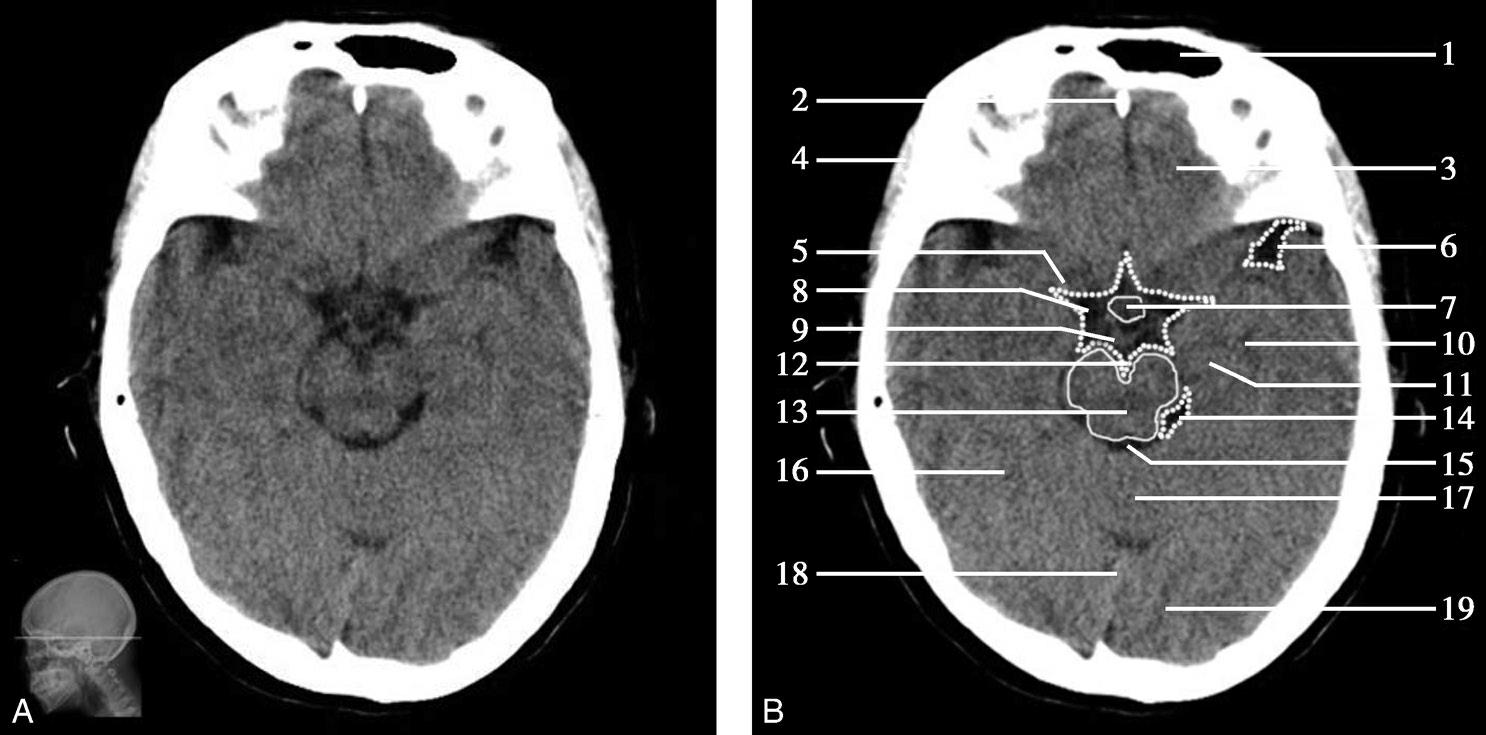

重要结构:卵圆孔、棘孔、破裂孔、斜坡、颞骨岩部、颈静脉孔(图1-2-1、图1-2-2)。

图1-2-1 颅底层面

A.横断面;B.横断面标注

1.晶状体;2.筛窦;3.颞肌;4.中颅窝底;5.外耳道;6.延髓;7.乙状窦;8.小脑半球;9.眼球;10.眼眶;11.上颌窦;12.蝶窦;13.乳突;14.耳郭;15.小脑蚓部;16.枕内隆凸

层面前部呈开口向前的“V”字形,正中为鼻中隔,向两侧依次为筛窦和眼眶,眼眶内前部为眼球,后部为眶脂体。翼腭窝位于眼眶后部,窝内含有脂肪并有上颌神经通过。层面中部为蝶骨体,蝶骨体中部可见含气蝶窦,蝶窦后方为枕骨基底部,两者呈前后关系,其上面构成斜坡。蝶窦两侧为蝶骨大翼,其后外侧缘处由前向后可见卵圆孔和棘孔,分别有下颌神经和脑膜中动脉通过。斜坡外侧、岩骨尖前方为破裂孔。蝶骨大翼与眶外侧壁的颧骨借颧弓相连,颧弓和蝶骨大翼之间有咬肌及颞肌。层面中部外侧为外耳道。颞骨岩部呈“八”字形,相互之间借破裂孔软骨、蝶岩软骨结合和岩枕软骨结合连接。岩部后外侧的乳突部内可见乳突小房,乳突部与枕骨相接。岩骨后部可见颈静脉孔,内有颈内静脉、舌咽神经、迷走神经和副神经通过。层面后部为颅后窝,其内可见延髓,延髓前方为延髓前池,内有椎动脉,后外侧为小脑半球下部,后方为第四脑室、小脑扁桃体及小脑蚓部。